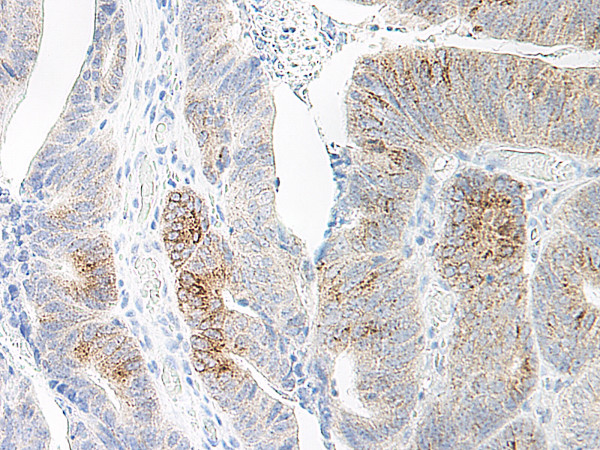

Product information "Anti-CCL20"

| Application: | ELISA, WB, IHC (paraffin) |